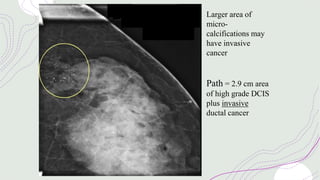

Larger area of

micro-

calcifications may

have invasive

cancer

Path = 2.9 cm area

of high grade DCIS

plus invasive

ductal cancer